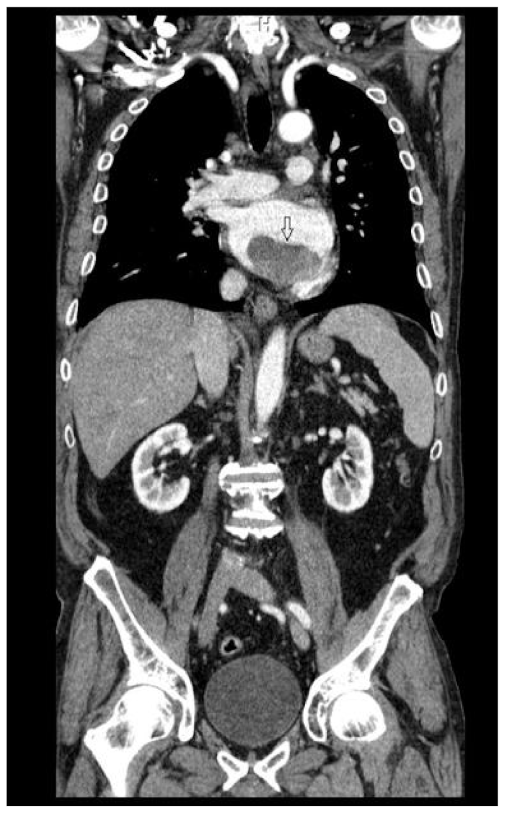

2.2. Preoperative Findings